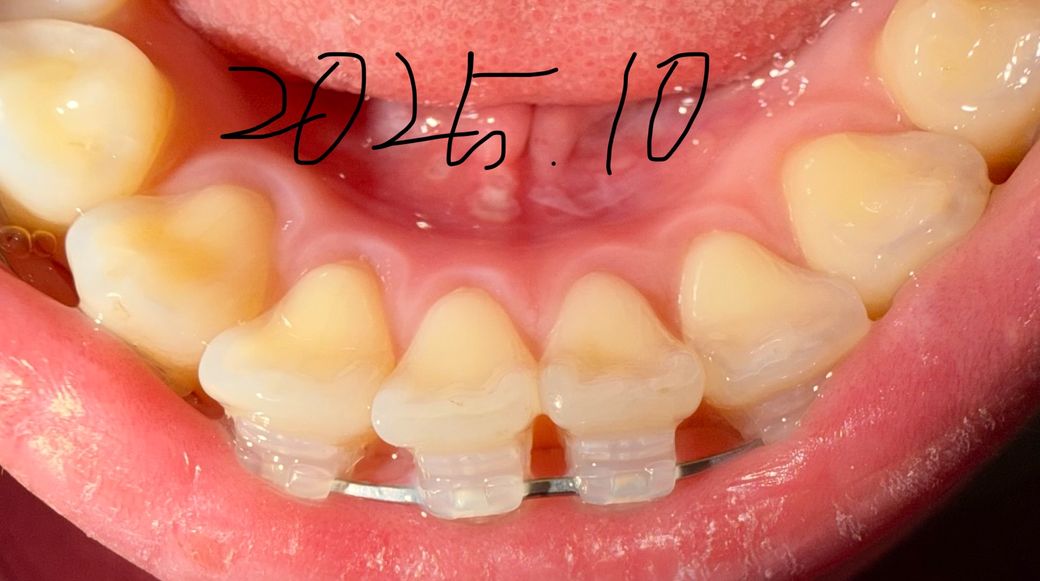

잇몸퇴축이 시작된거같아요 예방하고싶어요

교정한지 1년됐어요

잇몸퇴축 최대한 막으려면 어떻게해야하나요? ㅠㅠ

다른 잇몸퇴축이미지는 잇몸주변에 구내염처럼 흰 띠가 없는데, 저는 왜 흰 테두리가 있나요?

교정하기전부터 옅게 있었는데 아프지않아요

• 2번 째 사진

현재 보이는 정도로는 잇몸 퇴축이라고 할 수 없습니다. 교정 중에는 치아가 이동하므로 이동하면서 보이는 부분이 달라져 마치 퇴축된것처럼 보일 수도 있습니다. 하지만 지금과 같은 상태에서는 퇴축이 아닌 정상적인 상태로 보아야 하며 사진 상에서 병적 퇴축은 보이지 않습니다.

사진에 보이는 흰띠는 치아가 이동하면서 잇몸이 눌리면서 생기는 증상입니다. 교정을 하게 되면 잇몸이 조금씩 내려가는 경우가 있습니다. 교정으로 인해서 잇몸이 내려가는것을 막는 방법은 없습니다. 하지만 잇몸에 염증이 생기지 않도록 관리를 잘 한다면 잇몸퇴축이 더 일어나는것을 방지할수 있습니다.